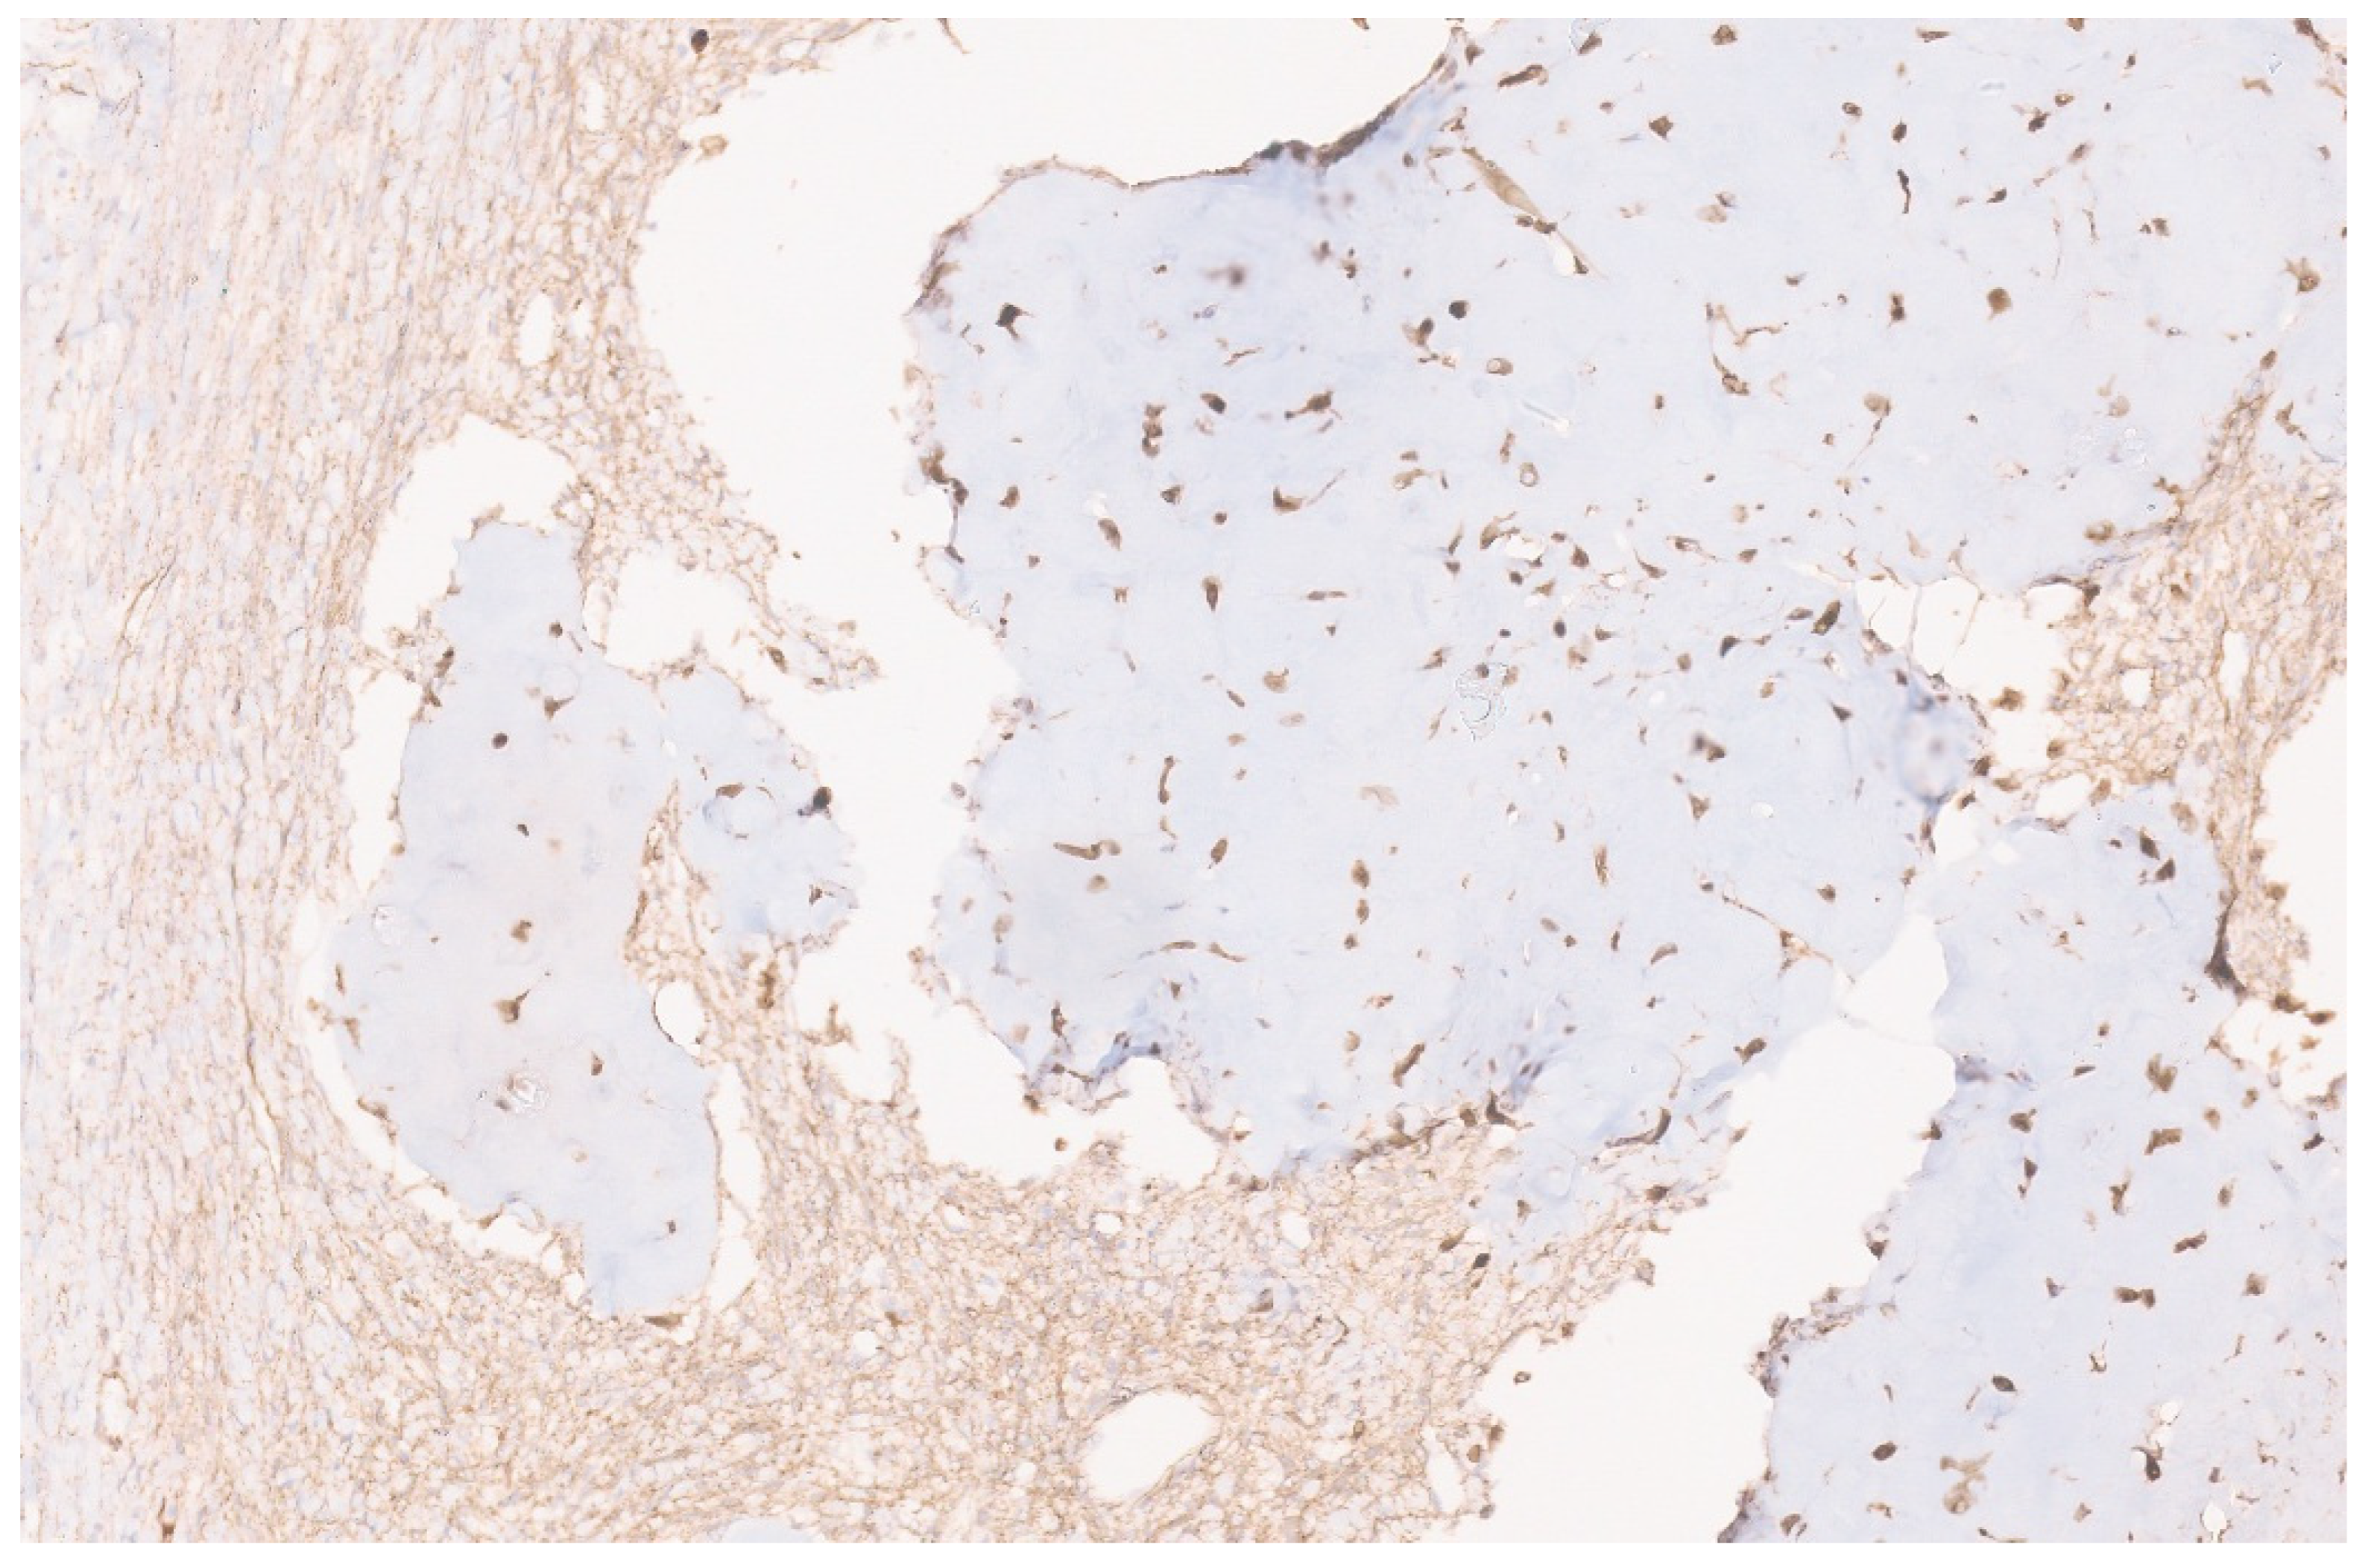

10.3. Pathology